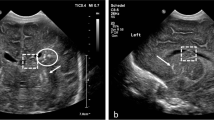

In case 1, US demonstrated bilateral ventriculomegaly and parenchymal calcifications without microcephaly. At MRI, performed at 28.4 weeks of gestation (Fig. 2), the vermis was very small; the supratentorial space demonstrated occipital subependymal pseudocysts, ventriculomegaly, diffuse polymicrogyria, opercular dysplasia and abnormal cortical intensity consistent with laminar necrosis.

Case 1. Brain MRI at 28 weeks of gestation. a–d T2-weighted sagittal (a, b) and coronal (c), and T1-weighted coronal (d) slices. The vermis is small and does not demonstrate normal morphology. The bulge of the pons is present. Both lateral ventricles are dilated, with visibility of large occipital subependymal pseudocysts (arrow in b). There is bilateral opercular dysplasia. The cortex is irregular (arrowhead in c), which suggests diffuse polymicrogyria. T2-hypointense and T1-hyperintense areas (dotted arrows in c and d) of the cortex are consistent with calcifications in the setting of laminar necrosis

In case 2, US showed marked microcephaly, ventriculomegaly with large occipital subependymal pseudocysts, absent corpus callosum and cavum septi pellucidi and parenchymal calcifications. At MRI, performed at 31.1 weeks of gestation (Fig. 3), all these findings were confirmed and MRI also revealed associated brainstem and cortical abnormalities.

Case 2. Brain MRI at 30 weeks of gestation. a–d T2-weighted sagittal (a, b) and coronal (c), and T1-weighted axial (d) slices are shown. The bulge of the pons is not visible on the midline sagittal slice (a) and the primary fissure (arrow) is too wide. The supratentorial space is very small and the pericerebral space is enlarged. The occipital subependymal pseudocysts are well visible (arrow in b). The corpus callosum and the cavum septi pellucidi are not seen. Note the bilateral opercular dysplasia and a very thin and irregular cortex, consistent with diffuse polymicrogyria. The normal sulcation is absent. In some areas, marked cortical T2 hypointensity (dotted arrow in c) and T1 hyperintensity (arrowhead in d) are suggestive of calcifications